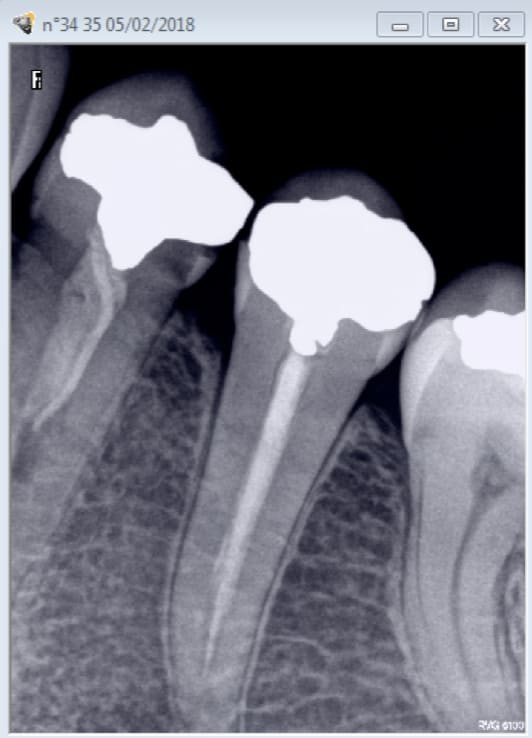

Radiographie d'un secteur ( 25)

Capture d écran 2018 03 15 15.13 - Eugenol

Radio graphie d'un secteur (36) . Ca fait 2 secteurs. Tu es toujours en argentique Cyber ? -)))

par contre celle là compte pour du beurre. -)))

Capture d écran 2018 03 15 15.18 - Eugenol

Capture d écran 2018 03 15 15.42 - Eugenol

HBQK191

Radiographies intrabuccales rétroalvéolaires et/ou rétrocoronaires de 2 secteurs distincts de 1 à 3 dents contigües

RadiographieS... il en faut au moins 2.

Par contre , deux bitewings G D avec 15 16 17 / 45 46 47 / 35 36 37/ 25 26 27 = HBQK443

Radiographies intrabuccales rétroalvéolaires et/ou rétrocoronaires de 4 secteurs distincts de 1 à 3 dents contigües

C'est du francais.